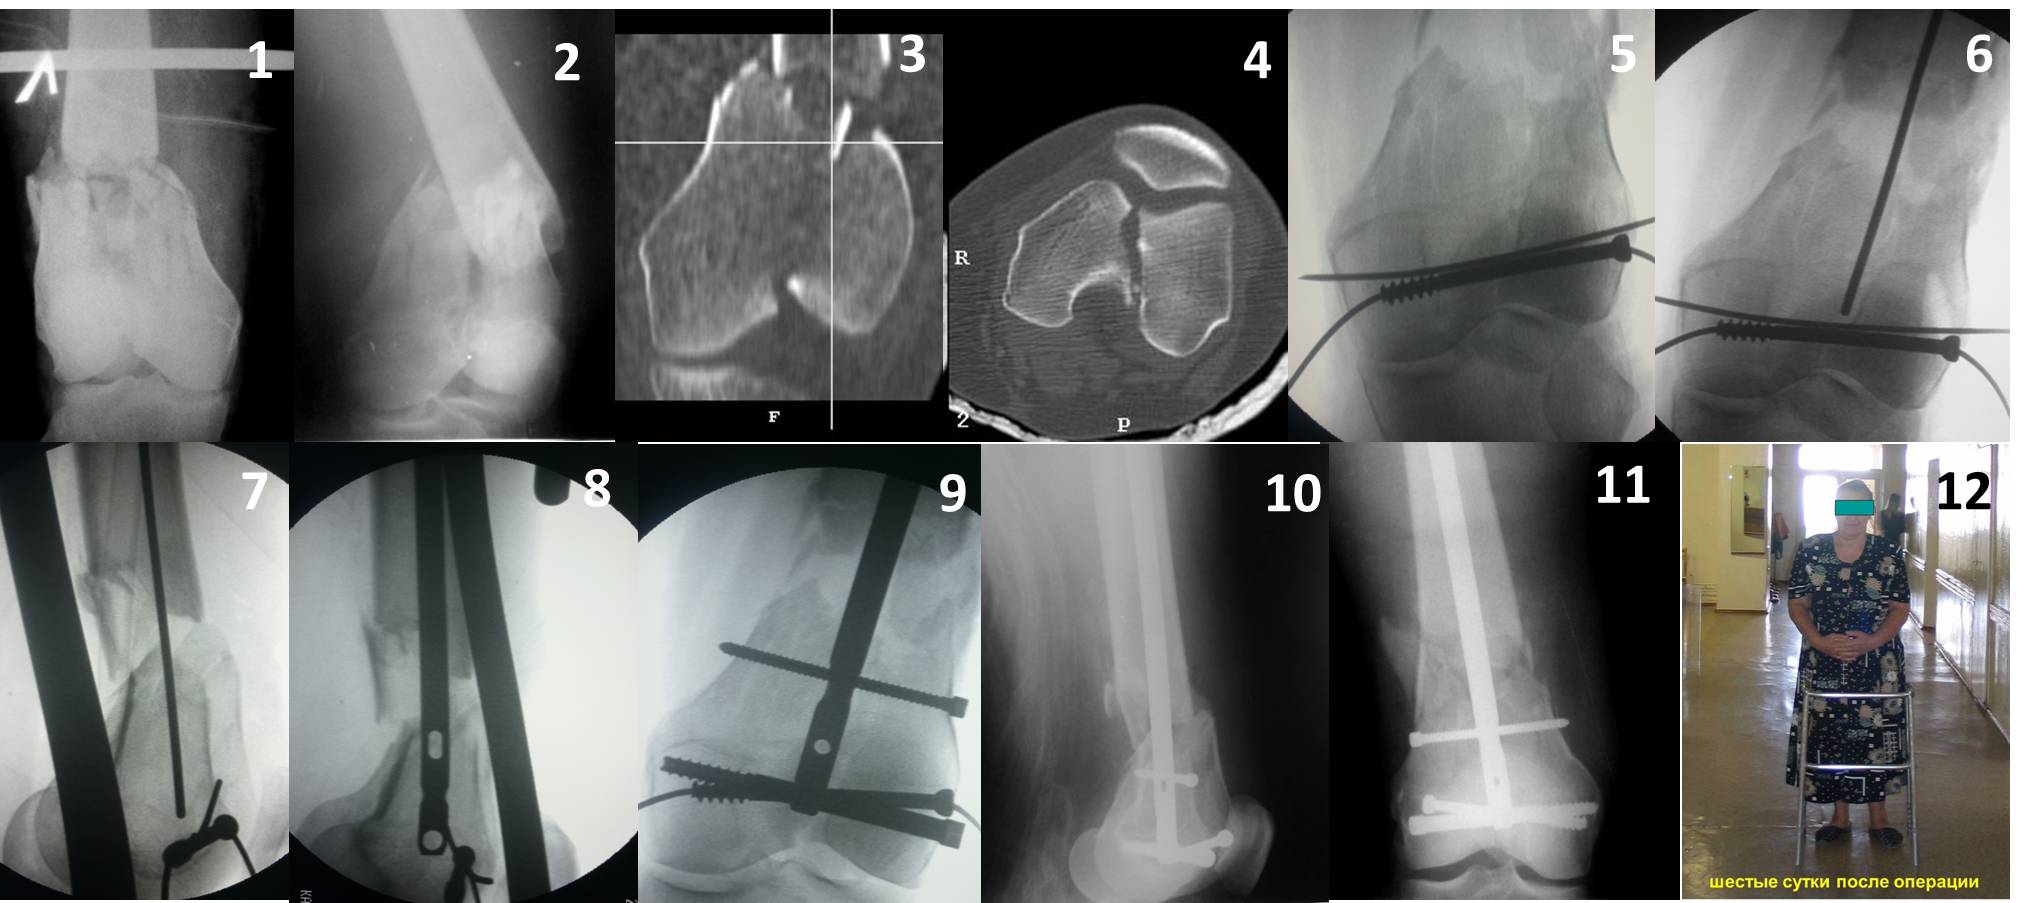

Ответ на эту часть Вашего поста – вложенный файл. Больная оперирована неделю назад по поводу открытого перелома дистального эпиметафиза бедренной кости. После операции она идёт в рентгенкабинет для выполнения послеоперационной контрольной рентгенографии, представленной на слайдах 10 и 11. Узнав, почему её фотографируют, просила передать Вам, Антон, привет.

В приложении пример недавней операции, C3, открытая репозиция, фиксация мыщелков спицами и винтами, ретроградный синтез большеберцовым гвоздем 10,5 мм диаметром, винты 5 мм.

Позволю себе напомнить коллегам ещё раз, что являюсь сторонником антеградного остеосинтеза при переломах дистального эпиметафиза бедренной кости. Такая приверженность основана не на преимуществах внесуставного введения стержня или большем проценте положительных результатов. Она основана на возможности обеспечить блокирование на минимальном расстоянии от суставной поверхности в нескомпрометированной кости и, таким образом стабилизировать максимально низкие переломы. В приведенном Вами случае самый дистальный из блокирующих винтов проведен на расстоянии более 2 см от конца стержня. Из-за того, что к стержню присоединяется кондуктор, на стержне теряется 1-1,5 см его длины, где можно было разместить отверстия для блокирования. И что более важно, вместе с потерянной для этой цели длиной стержня утрачивается для размещения блокировочных винтов, пожалуй, самая ценная часть дистального эпиметафиза бедренной кости. Проблемы дистального блокирования в разных плоскостях, локализации точки ввода стержня при антеградном остеосинтезе – это всё решаемые технические проблемы. Но антеградный остеосинтез низких дистальных переломов бедра при адекватном блокировании в нескомпрометированной кости обеспечивает решение стратегической задачи – стабильный остеосинтез и возможность нагрузки.